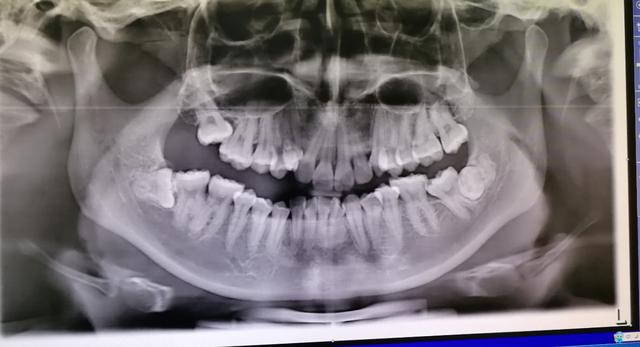

这位顾客年龄36、7岁这样,长期以来都在我诊所洗牙齿,他的牙齿挺好没有什么大的问题,就是智齿长歪了经常发关,每年都要帮他做他做冠周冲洗四、五次

他智点牙根很长,离下牙槽神经很近,我给他拍过口腔ct发现,牙根和神经管之间有一点重叠,牙根与神经管之间没有骨质阻挡,于是我建议他做截冠助萌,等牙齿根离开神经管远一点以后再拔牙齿,这样分两次处理虽然麻烦一点,但是很安全